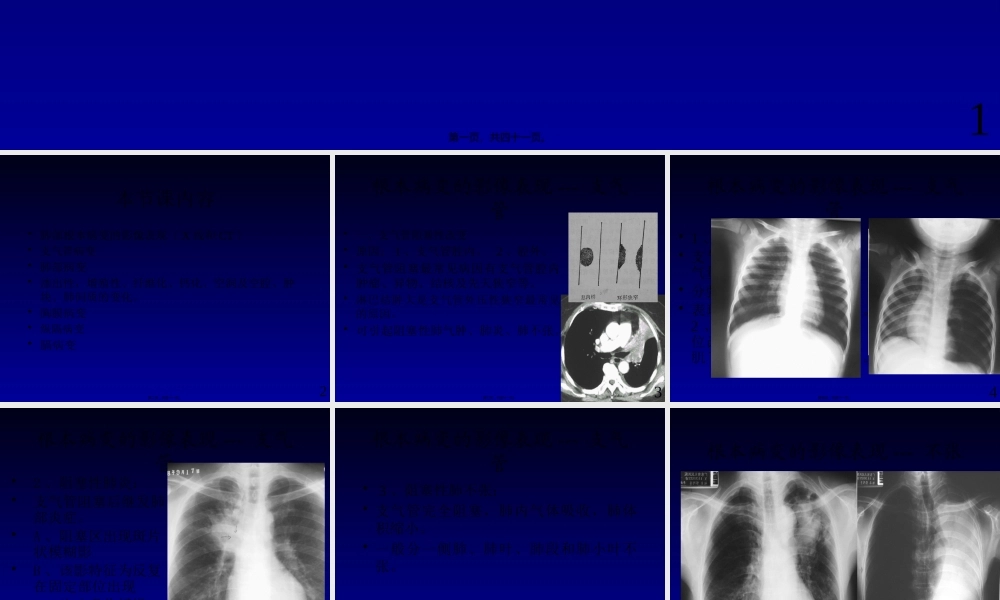

呼吸系统影像学诊断-----根本病变广东省人民医院影像医学部放射科赵振军1第一页,共四十一页。本节课内容•肺部根本病变的影像表现〔X线和CT〕•支气管病变•肺部病变•渗出性,增殖性、纤维化、钙化、空洞及空腔、肿块、肺间质的变化。•胸膜病变•纵隔病变•膈病变2第二页,共四十一页。根本病变的影像表现---支气管•一、支气管阻塞性改变•原因:1、支气管腔内。2、腔外。•支气管阻塞最常见病因有支气管腔内肿瘤、异物、结核及先天狭窄等。•淋巴结肿大是支气管外压性狭窄最常见的原因。•可引起阻塞性肺气肿、肺炎、肺不张。3第三页,共四十一页。根本病变的影像表现---支气管•1、阻塞性肺气肿:•支气管活瓣性狭窄,肺含气量增多。•分弥漫性和局限性•表现为1、肺透明度加大。2、肺纹理稀疏。3、占位改变:肋间隙增宽,膈肌下降、纵隔对侧移位等。4第四页,共四十一页。根本病变的影像表现---支气管•2、阻塞性肺炎:•支气管阻塞后继发肺部炎症。•A、阻塞区出现斑片状模糊影•B、该影特征为反复在固定部位出现•C、治疗吸收缓慢。5第五页,共四十一页。根本病变的影像表现---支气管•3、阻塞性肺不张:•支气管完全阻塞,肺内气体吸收,肺体积缩小。•一般分一侧肺、肺叶、肺段和肺小叶不张。6第六页,共四十一页。•直接征象:病变区域均匀密度增高影。•间接征象:体积收缩,如胸廓塌陷,肋间隙变窄,纵隔向患侧移位,肺门移位和膈肌升高等。根本病变的影像表现---不张7第七页,共四十一页。•轮廓征根本病变的影像表现---中叶不张8第八页,共四十一页。•“S征〞•反写“S〞根本病变的影像表现---不张9第九页,共四十一页。根本病变的影像表现---肺部•二、肺部病变•1、渗出性病变:•肺泡内气体被渗出液和少量细胞取代。•表现为边缘模糊的密度增高影。10第十页,共四十一页。•斑片、模糊•腺泡内渗出呈斑点状;•小叶渗出为斑片状;•肺段和肺叶渗出为大片状实变影,影内可见支气管气像。11第十一页,共四十一页。根本病变的影像表现---肺部•2、增殖性病变:•肺泡内细胞积聚,可形成肉芽肿。•表现为边缘较清楚的密度增高影,呈结节状、球形或肿块状。12第十二页,共四十一页。根本病变的影像表现---肺部•3、纤维化:•肺组织被纤维组织取代。•表现为结节状、索条状和斑块状等,但边缘清楚,高密度影。•纤维化可引起肺门及纵隔向患区移位,肋间隙狭窄,膈肌升高等。13第十三页,共四十一页。根本病变的影像表现---肺部•4、...